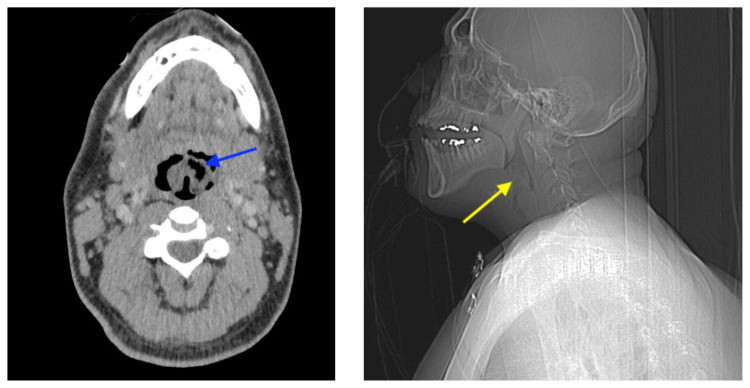

At the time of presentation to the ED, laboratory results were significant for leukocytosis to 11.8 × 109 white blood cells/L and a partial pressure of carbon dioxide of 52 mmHg on venous blood gas. Computed tomography (CT) of the soft tissue of the neck with contrast showed edematous swelling of the epiglottis and aryepiglottic fold with internal foci of gas (blue arrow) and partial effacement of the laryngopharyngeal airway and scattered cervical lymph nodes bilaterally (Figure 1). Findings were consistent with epiglottitis containing nonspecific air. Additionally, the pathognomonic “thumbprint sign” (yellow arrow) was found on lateral x-ray of the neck (Figure 2). The CT findings as shown in figure 3 illustrate lateral view of the swelling of the epiglottis, gas, and blockage of the airway.